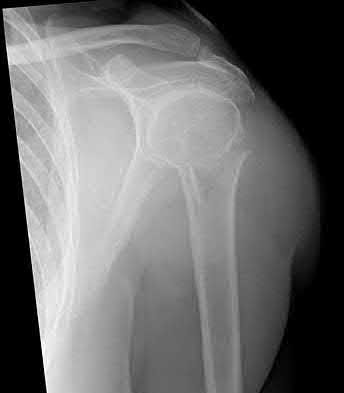

3. # Which of the following is not an appropriate implant for treatment of the fracture seen in Figure A?

5. Sliding hip screw Corrent answer: 5

The image shows a reverse obliquity intertrochanteric hip fracture.

According to the referenced article by Haidukewych et al, unstable peritrochanteric hip fractures have a worse outcome (failed in 9/16 cases) if treated with a sliding hip screw. Two additional factors that were found to have a strong correlation with postoperative failure (nonunion, loss of reduction) were poor reduction and poor implant placement. In this study, fixed angle devices were superior. Intramedullary fixation has the added advantage of a shorter lever arm and less potential for fracture collapse and limb shortening.

The IMN also acts as a medial buttress.

According to Sanders et al, the dynamic condylar screw (DCS) can also be used in subtrochanteric models, but should not be used if extensive comminution is seen, as they reported a high failure rate with DCS in these fractures if highly comminuted. They report a 77% overall union rate with this device.